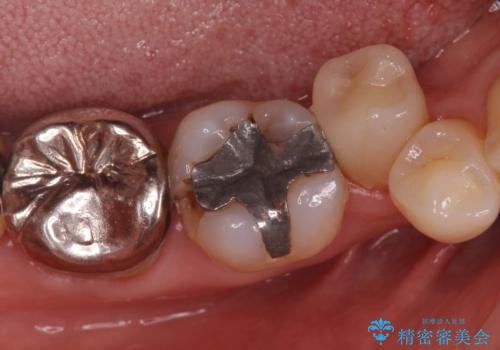

視診だけではわかりづらいですが、レントゲン画像にて昔の詰め物の下に虫歯があることがわかります。

以前樹脂を詰めた結果再び虫歯ができてしまっていることから、同じ治療は同じ結果になる可能性があるため今回はアプローチを変えてセラミックインレーで修復処置をしていくこととなりました。

虫歯の取り残しや、不適合な詰め物は再治療のリスクとなります。